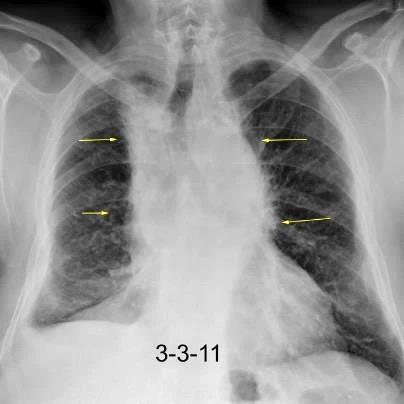

Triada de Garland

Ganglios paratraqueales derechos e hiliares bilaterales

95% de pacientes tienen ganglios hiliares bilaterales aislados o con afectación mediastínica (espec. paratraqueal derecho).

Criado E et al. Pulmonary sarcoidosis: typical and atypical manifestations at high-resolution CT with pathologic correlation. Radiographics. 2010